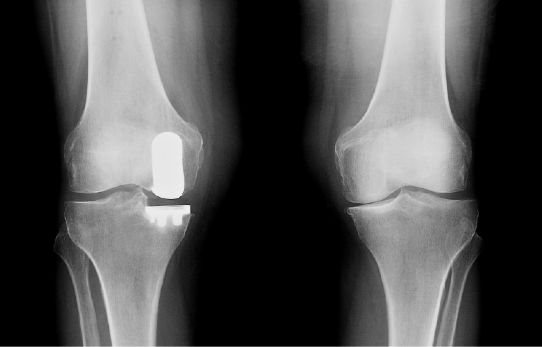

Based on the severity of the arthritis in the knee, total or partial knee replacement may be recommended by a surgeon. Both procedures involve the orthopaedic surgeon guiding the Mako Robotic-Arm to remove diseased bone and cartilage.

Mako Robotic-Arm Assisted Partial Knee replacement is a treatment option for adults living with early to mid-stage osteoarthritis (OA) that has not yet progressed to all three compartments of the knee.

In comparison, Mako Robotic-Arm Assisted Total Knee replacement is a treatment option for adults living with mid to late-stage osteoarthritis of the knee. With Mako Total Knee replacement, the entire knee joint is replaced and the surgeon inserts a Triathlon Total Knee implant. With over a decade of clinical history, Triathlon knee replacements are different than traditional knee replacements because they are designed to work with the body to promote natural-like circular motion.